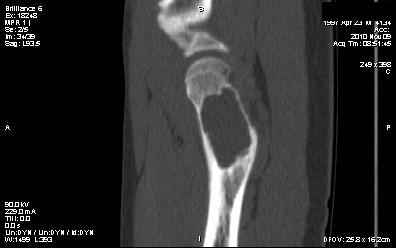

Киста шейки бедра

Мальчик 13 лет. В течение нескольких месяцев беспокоят боли в левом тазобедренном суставе.

При обследовании выявлена киста шейки левого бедра с сопутствующими изменениями в головке бедра, которые мы трактуем как дистрофические. Планируем вскрытие и санацию полости кисты передне-боковым доступом, костную пластику. Перед нами возникли следующие вопросы: для пластики использовать крыло подвздошной кости либо большеберцовую кость,либо их комбинацию, (полость большая,одним крылом можно не обойтись) или донорский аллотрансплантат с Коллапаном? Фиксировать ли? Если фиксировать, то чем? Доступны обычные угловые пластины либо АВФ.

Ув. Сергей! Д-з: или солитарная киста, или аневризмальная (есть небольшое "вздутие") или остеобластома ( старое название "остеобластокластома"). Если 3 вариант то полость надо обработать спиртом или азотом. Предпочтительнее аутопластика из 2 подвздошных костей. Так как срок фикс. длительный то АВФ субоптимален. Предпочтительнее фиксация угловой нестандартной пластиной 110-115 град ("разогнутая" 95 град).В запасе минимум 3 пластины с 3 типоразмерами клинка (расстояние от tuberc. innominatum до перехода метаэпифиза в нижний полюс головки).Ножка: минимум 3 винта в "здоровой" кости диафиза.Перед формированием канала пробойником 3 "страховочные" спицы: большой вертел центр головки (межвертельный перелом лучше перелома шейки) Аутопластика после МОС.

Выполнили, что и запланировали. Обошлись одним крылом. Зафиксировали пластиной. Мысль о возможной фиксации TEN приходила, но... доступны только гвозди Эндера. А ими - не решились.